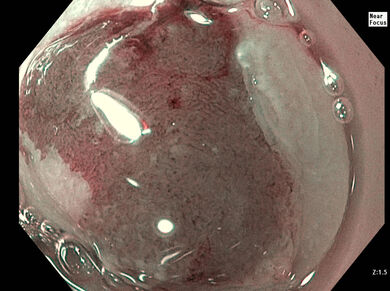

Ein 87-jähriger kardial vorerkrankter Patient wurde mit einem Hb von 5.9 g/dl unter Teerstuhl bei bekannter Eisenmangelanämie nach Auftransfusion zur endoskopischen Abklärung vorgestellt. Seit mehreren Jahren erfolgte eine orale Eisensubsitution mit einem unbekannten Präparat. In der ÖGD fand sich eine schwere, H.p. negative erosive Gastritis mit multiplen Erosionen. Eine Sickerblutung wurde mit 3 Clips versorgt.

Nach 2 Monaten unter PPI-Therapie und fortgesetzter Eisensubstitution mit anhaltender Anämie (Hb 9.2 g/dl) fanden sich im Magen noch immer vereinzelte Erosionen (Bild links) und partikelförmige graue Einsprengungen (Bild rechts).